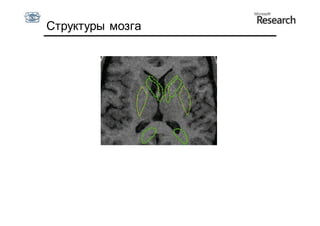

Пример 3: Структуры мозга

Структуры мозга

• 72 примера

• 123 точки

• 5000 пикселей

Начальное положение   Результат